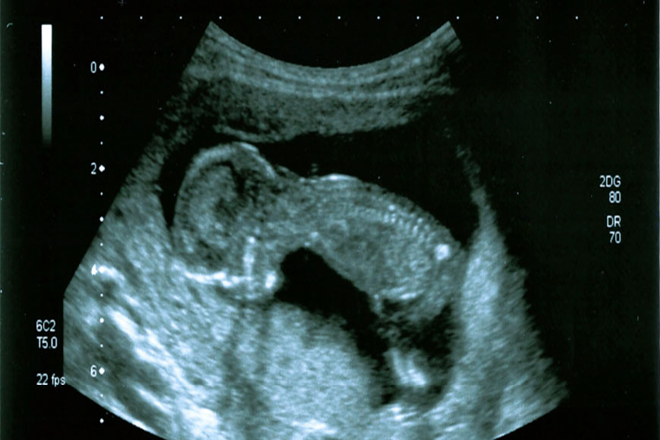

Los defectos congénitos afectan al 2-3% de los recién nacidos vivos. La translucencia nucal es la acumulación de líquido en la región posterior del cuello del feto en el primer trimestre del embarazo. Esta se utiliza como tamiz para trisomía 21 debido a su fuerte asociación con esta condición. Se evaluó el resultado perinatal de pacientes con translucencia nucal igual o mayor al percentil 95 para la longitud cráneo-caudal, que fueron referidos al servicio de Genética para un cariotipo fetal.

La medición de la translucencia nucal se realizó mediante ultrasonografía transabdominal. Los pacientes con valores iguales o superiores al percentil 95 fueron remitidos a asesoramiento genético. Aquellos con sospecha de cardiopatía fetal se sometieron a ecocardiografía. Al nacer, se efectuó una exploración física detallada por un médico genetista. Se establecieron dos grupos para el análisis: pacientes con cariotipo anormal y pacientes con cariotipo normal, este último se subdividió según los hallazgos.

La importancia de la ecografía en el primer trimestre, realizada entre las 11+0 y 13+6 semanas de embarazo, radica en la detección temprana de anomalías fetales. Durante las últimas décadas, el diagnóstico temprano ha mejorado notablemente la morbilidad y mortalidad asociada con embarazos ectópicos, permitiendo opciones de manejo menos invasivas. La ecografía temprana debe reservarse para casos clínicos específicos o ante la presencia de factores de riesgo.